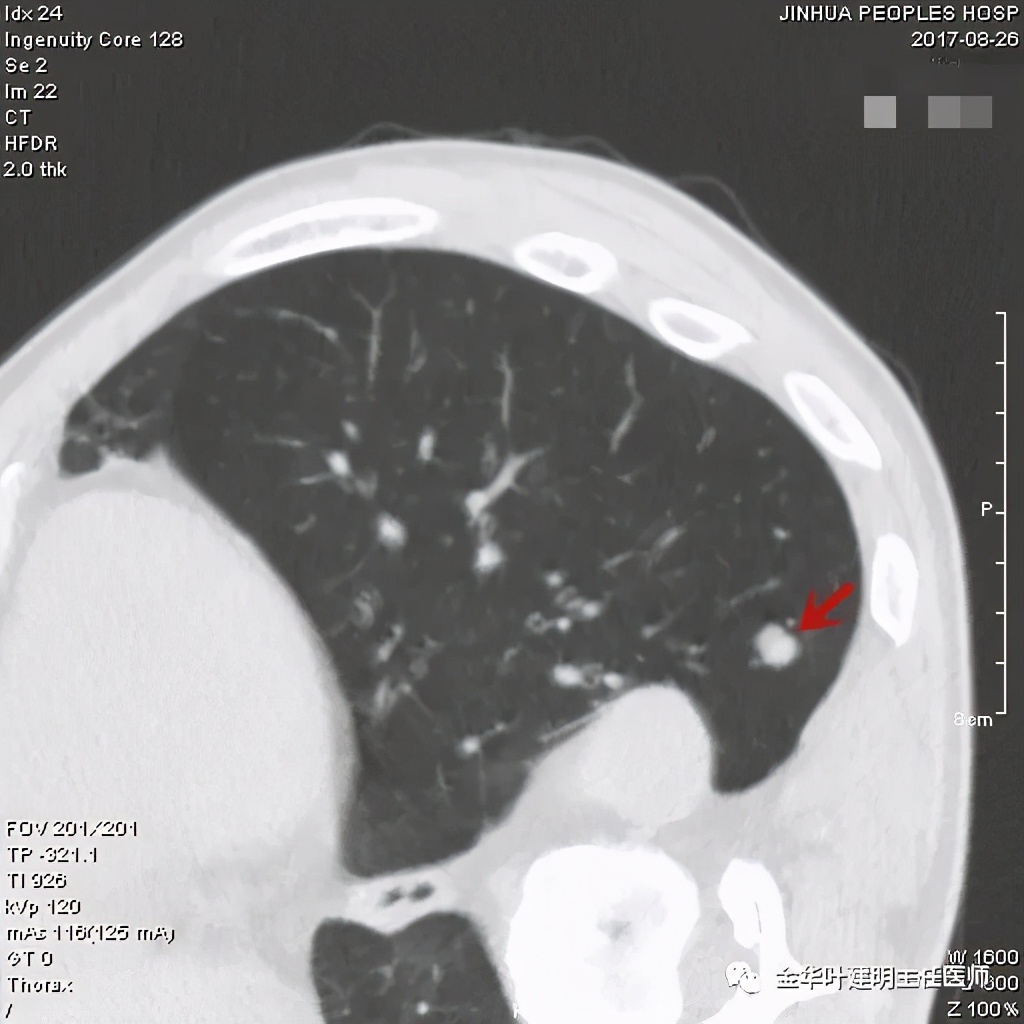

直径约2.4厘米,密度欠均,血管贴边,增强轻度强化。单从描述看,恶性可能性较大。我们再来看看图像:

可见右上叶占位,我们现在知道了结果以后回头看,发现病灶的边缘在各个层面都是过于光滑(绿色箭头所示)。血管紧贴病灶边走行(桔色箭头所指),是不是有侵犯看不清楚,若是靶扫描加重建可能会更清楚点。支气管感觉也是贴着病灶走,但有的层面是不是截断,也不看的不太清楚。有的层面见局部有点状高密度(蓝色箭头所指),是不是错构瘤的局部钙化呢?若是纵隔窗又是如何?

上图示病灶

上图示病灶密度不均

上图示病灶局部点状高密度(蓝色);边缘过于光滑(绿色)

上图示病灶密度不均,但边缘过于光滑(绿色);支气管似有截断(粉色);局部有点状钙化(蓝色)

上图也示病灶密度不均,但边缘过于光滑(绿色);支气管似有截断(粉色);局部有点状钙化(蓝色)